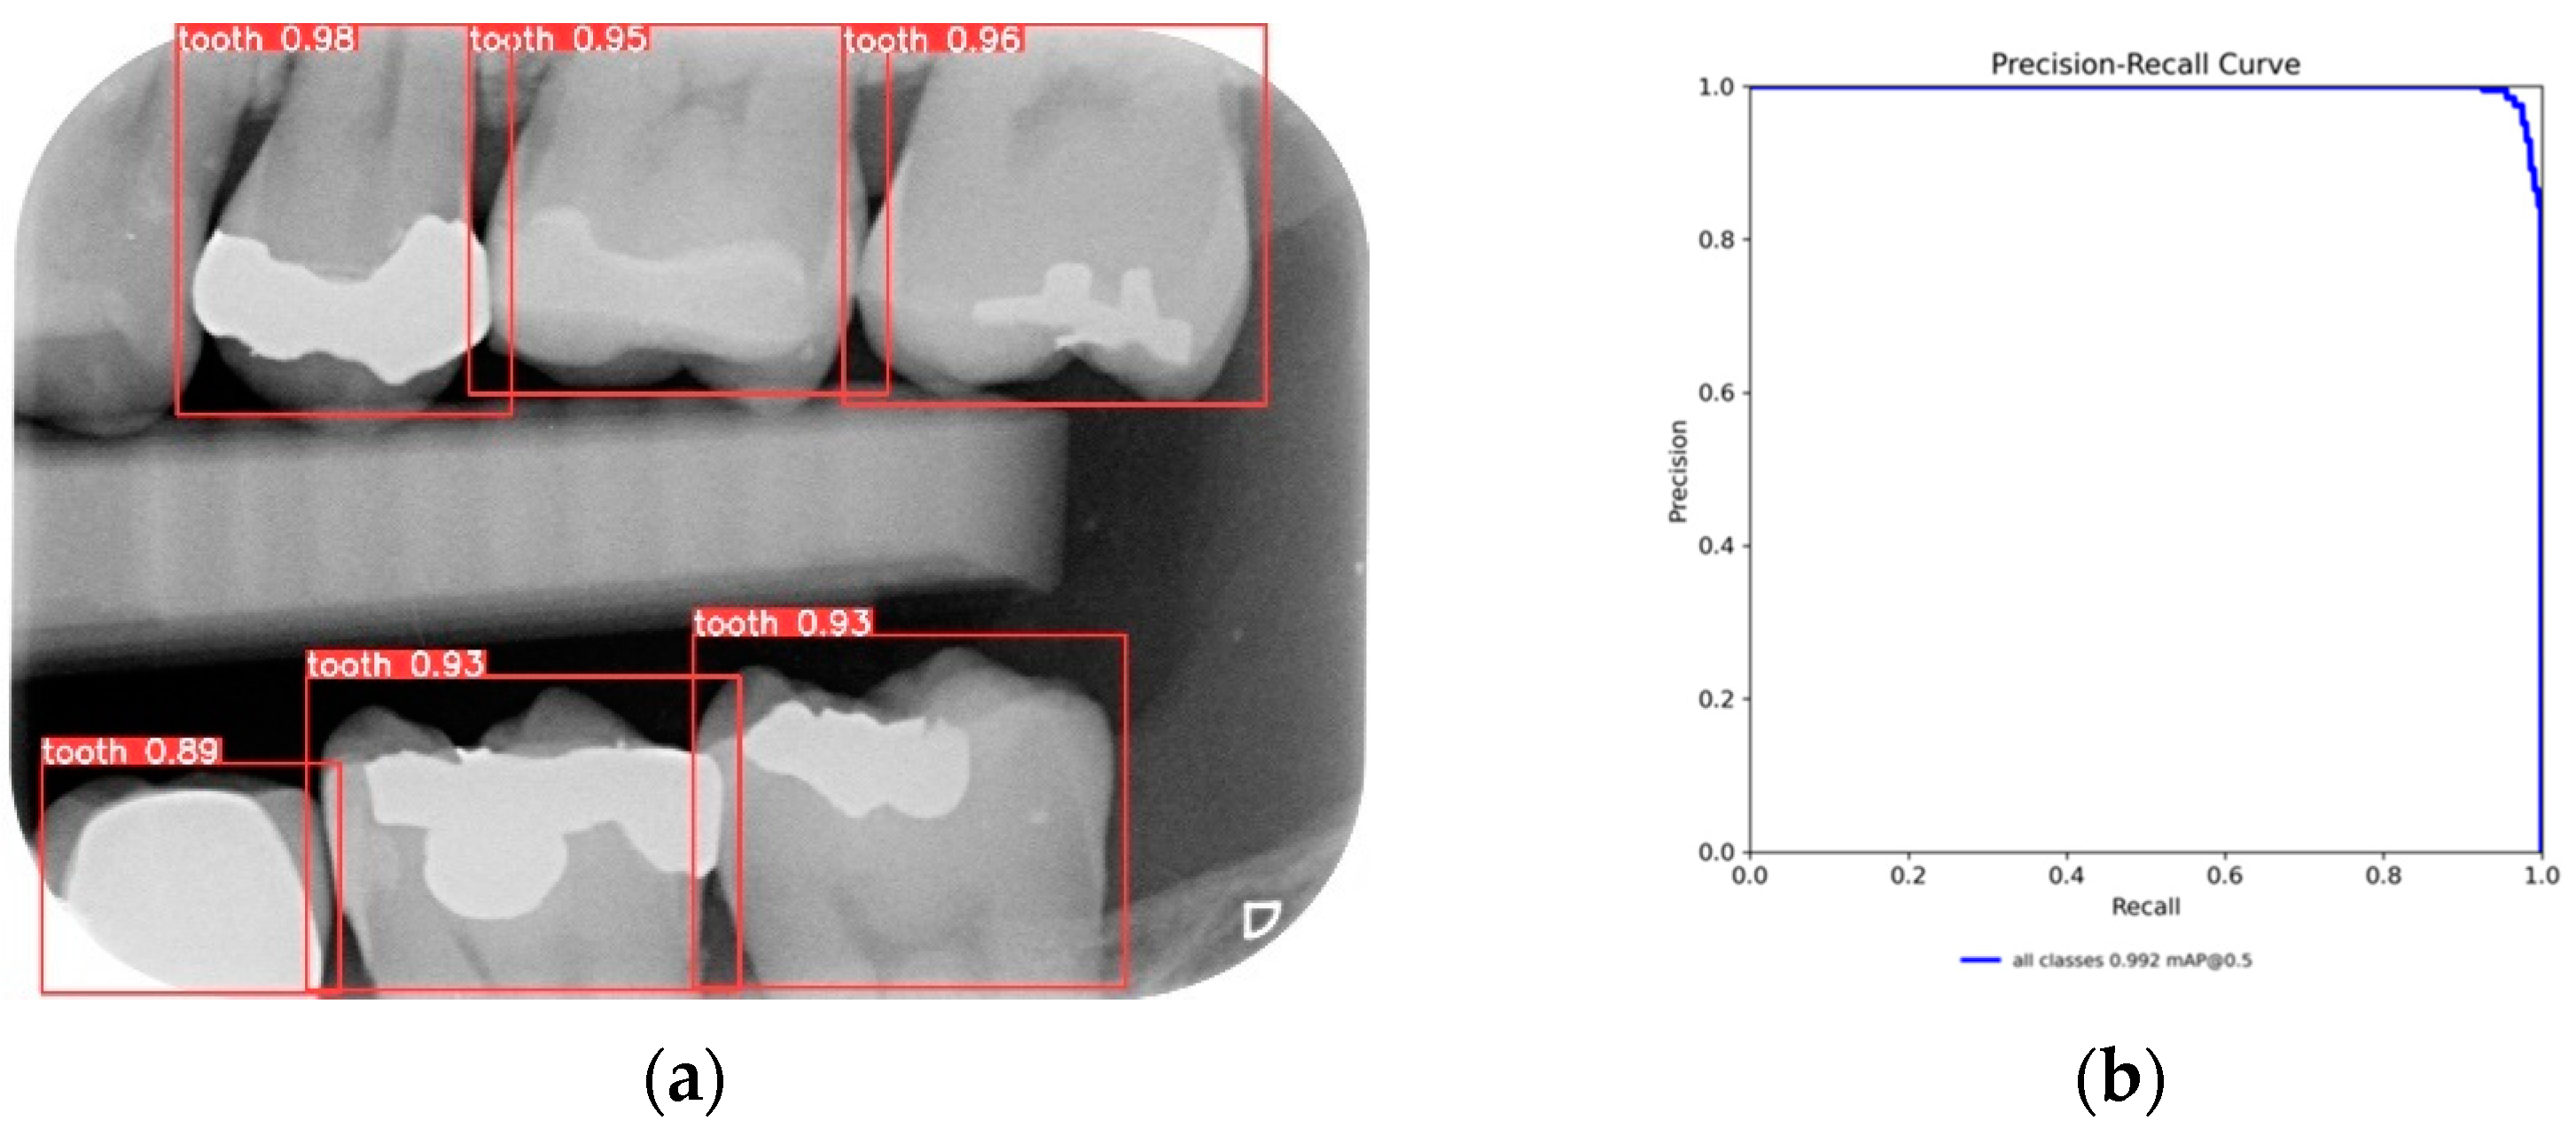

After training the YOLO object-detection models, this study tested unlabeled, and untrained the BW images. The test results are illustrated in Figure 10. The four object models used in this study, along with the image-augmentation technique, successfully identified all the teeth of interest in the BW images. After the image-segmentation stage, the extracted regions were delineated by the red boxes in Figure 10a, and the PR curve is shown in Figure 10b. The results extracted are depicted in Figure 11, effectively capturing the individual teeth and their edges and enabling further image-enhancement and CNN training steps.

Figure 10.

YOLO validation results: (a) YOLOv8 detect results; (b) YOLOv8 validation PR curve.

In the validation results, this study compared image-segmentation algorithms, and the results are shown in Table 9. It can be seen that the use of a YOLO object-detection model results in a better accuracy than that of a segmentation algorithm. Table 10 demonstrates that YOLOv8 achieves the highest precision and mAP values, reaching 97.48% and 99.37%, and Table 11 demonstrates a comparison with another research study. Meanwhile, YOLOv5 exhibits the best recall performance at 97.82%. This study also compares these results with those obtained using YOLO models in references [19,31]. The YOLO models proposed in this study show an improvement of up to 19% in feature detection and segmentation.